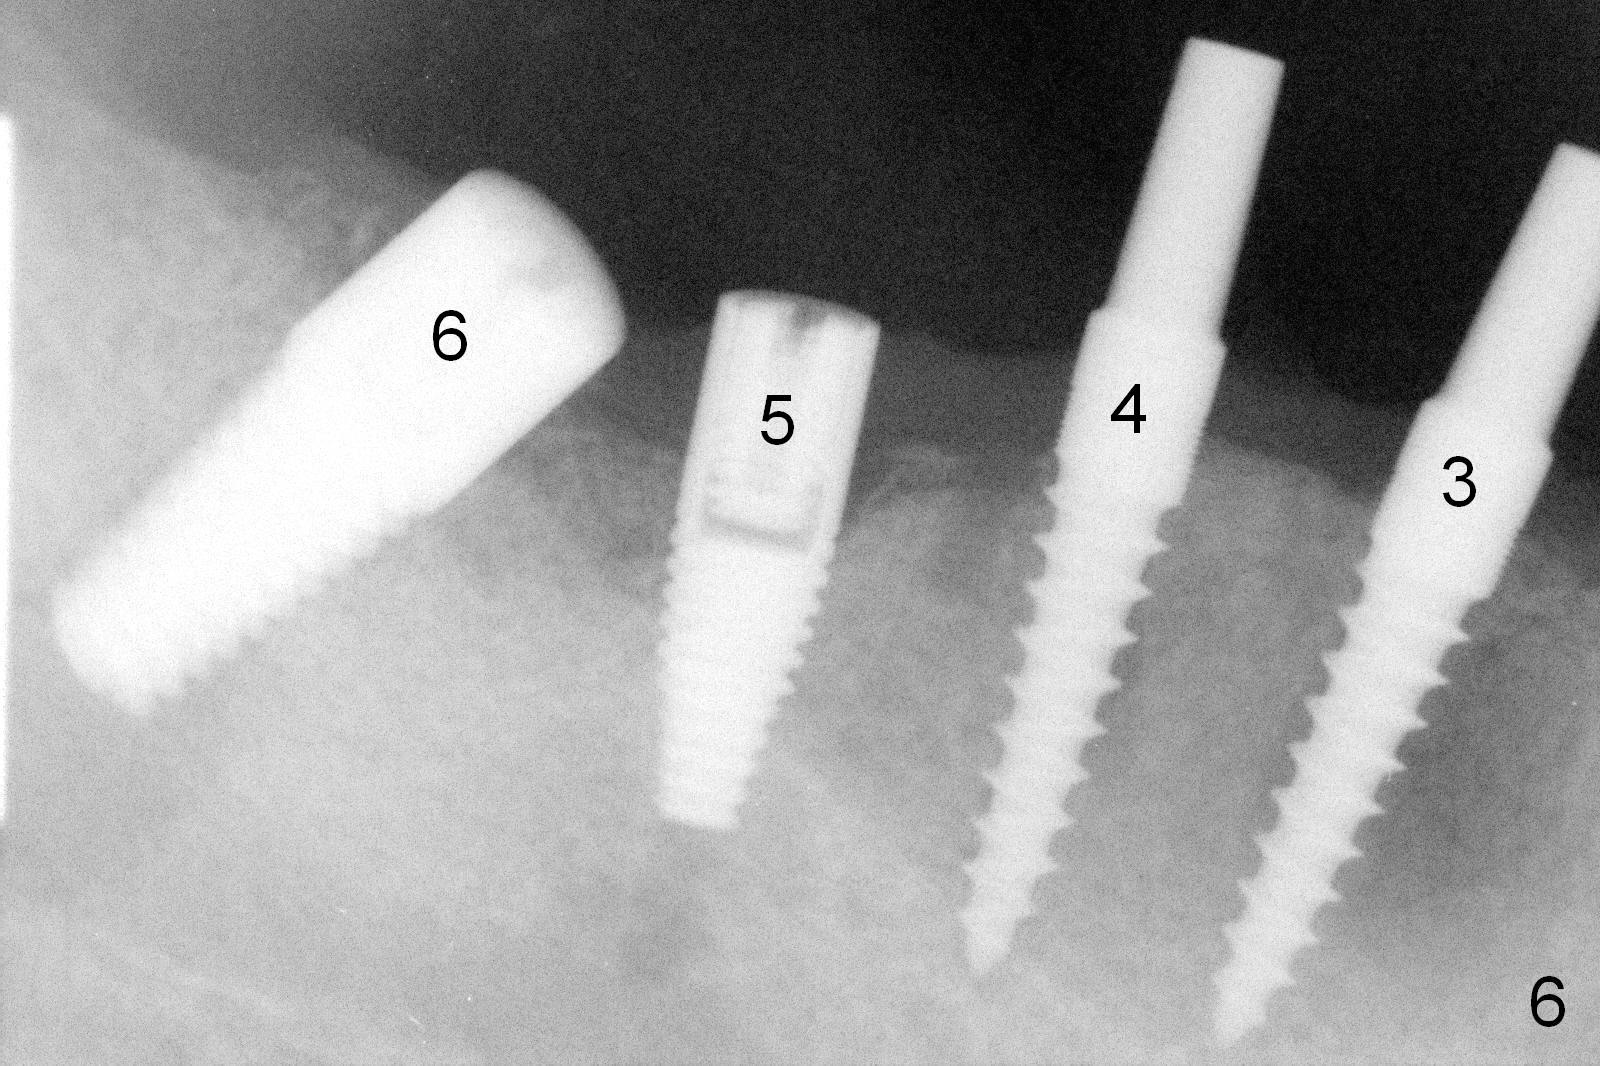

The lower right bridge (from canine (Fig.2: 3) to 1st molar (Fig.1: 6)) fails while a 77-year-old man is undergoing chemotherapy for urinary bladder cancer. The abutments of the bridge are extracted without plan for implants (Fig.4). Four months later, the patient returns for implants (Fig.3), but the ridge is narrow (Fig.5). While 2 of 3x14 mm 1-piece implant are placed at the canine and 1st bicuspid sites, 2 piece ones at the 2nd bicuspid and 1st molar sites (Fig.6: 3.5x11 mm, 5x14 mm). Soft (Fig.7-10) and hard (Fig.11) tissues heal 1 week (Fig.7) and 4 months (Fig.8-11). There is minimal bone resorption 1 year 7 months post cementation (Fig.12,13, non-splinting). It appears that narrow diameter implants are a valid solution to narrow ridge at the sites of the lower canine and premolar. As long as there are enough implants for function, the crowns are not necessary to be splinted. Surprisingly, the patient starts flossing after implant restoration. Retrospectively an immediate provisional bridge should have been fabricated.